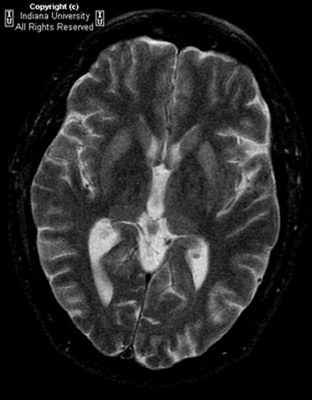

Болезнь Крейтцфельда–Якоба (БКЯ) является редким нейродегенеративным заболеванием, обусловленным накоплением патологической изоформы прионного белка. Классическая клиническая картина БКЯ характеризуется быстро прогрессирующей деменцией, атаксией, миоклонией, а также акинетическим мутизмом в терминальной стадии заболевания. Из инструментальных методов исследования ведущая роль в клинической практике принадлежит магнитно-резонансной томографии головного мозга. С 2014 по 2019 г. в Республике Саха (Якутия) авторы наблюдали 4 пациентов с вероятной БКЯ. У всех пациентов были примерно одинаковые возраст дебюта заболевания (50–60 лет) и начало с неспецифических церебральных симптомов. Однако последующее развитие быстро прогрессирующей деменции и других характерных признаков позволило предположить БКЯ. У пациентов выявлены показательные нейровизуализационные признаки в виде гиперинтенсивности хвостатых ядер и подушек таламуса в режимах FLAIR и DWI с образованием типичного сигнала «хоккейных клюшек», а также гиперинтенсивность серого вещества в режиме DWI (симптом «ожерелья Венеры»). У 3 пациентов заболевание закончилось фатально в течение года после его дебюта. Четвертая пациентка находится под домашним наблюдением (длительность заболевания 6 мес).

До недавнего времени «золотым стандартом» верификации диагноза БКЯ являлась биопсия головного мозга, позволяющая выявить характерные изменения в мозговой ткани в виде мелких вакуолей в телах нейронов, из-за чего ткань мозга приобретает губчатый вид, пролиферации клеток глии при отсутствии признаков воспаления. При электронной микроскопии возможно обнаружение прионных палочек, являющихся патогномоничным признаком заболевания. Указанные морфологические изменения отмечаются в коре головного мозга, базальных ганглиях, мозжечке и верхних отделах ствола мозга. Однако в случаях БКЯ биопсия мозга не нашла широкого применения в клинической практике из-за инвазивности метода, сложности санитарной обработки оборудования и утилизации биоматериалов, связанных с высокой устойчивостью прионов, а также вследствие небольшого объема биоптата мозговой ткани, что может быть причиной ложноотрицательных результатов морфологического и иммуногистохимического исследования. Однако в настоящее все больше распространена МРТ диагностика данного заболевания, по причине выявления специфических изменений, наиболее информативными являются последовательность DWI.

Магнитно-резонансная томография позволяет получить качественные и контрастные изображения головного мозга пациента. Во время проведения МРТ выявляются участки повышенного сигнала, локализованные в подкорковых ганглиях и таламусах. Кроме того, магнитно-резонансная томография дает возможность успешно определять признаки атрофических изменений мозжечка, коры головного мозга и расширение желудочковой системы.